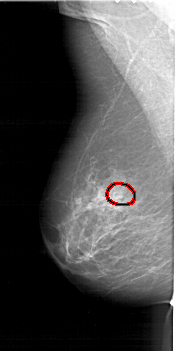

A_1415_1.LEFT_MLO

LEFT_MLO LINES 6316 PIXELS_PER_LINE 3151 BITS_PER_PIXEL 12 RESOLUTION 43.5 OVERLAY

FILE: A_1415_1.LEFT_MLO.OVERLAY

TOTAL_ABNORMALITIES 1

ABNORMALITY 1

LESION_TYPE CALCIFICATION TYPE PLEOMORPHIC DISTRIBUTION CLUSTERED

ASSESSMENT 4

SUBTLETY 3

PATHOLOGY MALIGNANT

TOTAL_OUTLINES 1

BOUNDARY